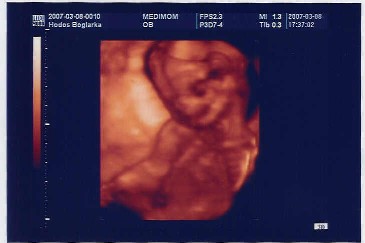

Én ma 16:30-ra megyek 4D-re, most lesz a genetikai UH is, holnapra rakok is fel képet!!!! Ma megtudjuk, hogy fütyis, vagy puncis

A MEDIMOM elérhetősége, aki kérte: MOM Park Földszint, Telefon: 06-1/ 887-43-33

Nyitvatartás: H-P 8-20-ig